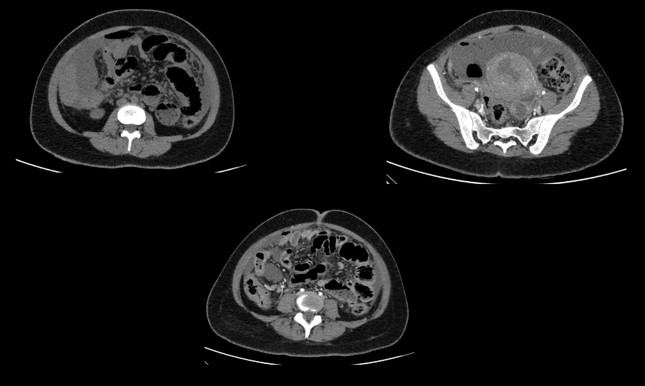

48 year old male Presented with history of 3 episodes of melena. No known comorbidities Gastro -Duodenoscopy - Erosive duodenitis Colonoscopy – unremarkable.

48 year old male Presented with history of 3 episodes of melena. No known comorbidities Gastro -Duodenoscopy -Erosive duodenitis Colonoscopy – unremarkable.